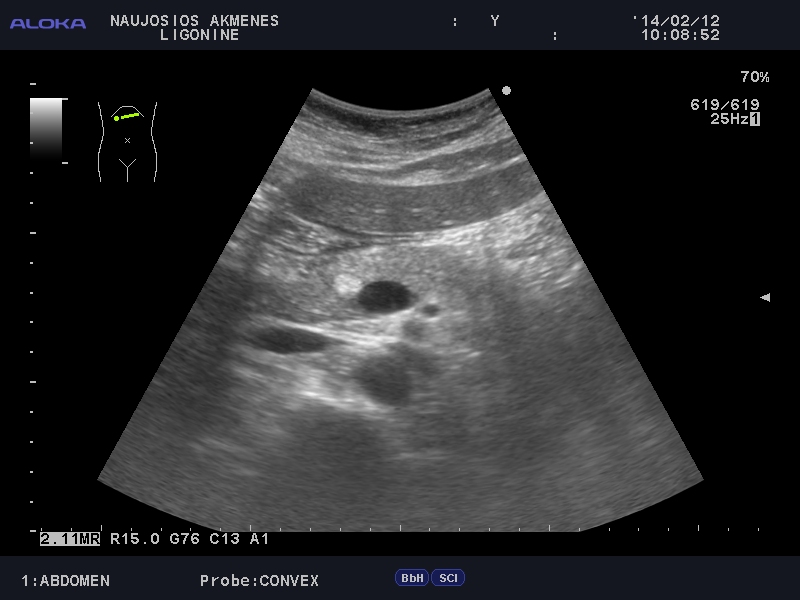

Очаг в панкреас

Мужчина средних лет. Жалоб нет.

qqqq_20140212_ABDOMEN_0011.JPG

Рекомендовал КТ.